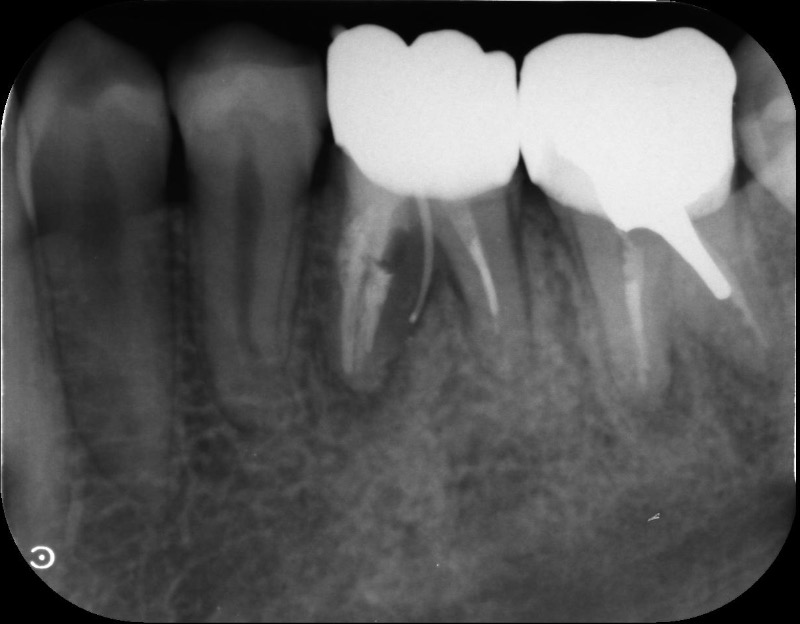

Q

N様主訴は前歯の隙間、形が気になる 上顎2の矮小歯と下顎前歯の歯軸が立っているのが気になるとの事でした上顎は拡大を行い、2の近遠心に隙間を作り最終的には補綴で形態を整える

下顎前歯部の歯軸を倒し被蓋を作る

という計画を立てました。

ところが左下の6の近心根が保存不可能になってしまい、近心根は抜根しか手がなくなってしまいました質問1

8番は真っ直ぐに生えていますが抜歯する計画で進めました

でも76が失活歯で左下は抜かないとならないときたので

もっといい治療計画ありますでしょうか質問2

8を抜く治療計画で進める場合

急性症状はないので左下6は抜かないでこのままにしてアライナー矯正を行い、矯正後に補綴を考えるのがいいのか

保存不可能な左下6近心根を抜いてから再度シュミレーションをするのがいいのか

左下6はこのままにして進める場合のシュミレーションは作りました -